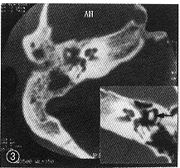

例2 女,19岁,以反复右耳流脓、听力下降13年,加剧1年于1998年7月13日入院。查体:右耳道见脓液,近鼓膜处上壁有一局限性隆起,紧张部穿孔,松弛部充血。CT示:右乳突气房混浊,鼓室、鼓窦及鼓窦入口等处见散在分布高密度影。锤骨砧骨吸收破坏,以砧骨明显(图3)。纯音测听:右耳语言频率平均气导:48 dB nHL,骨导正常。脓液培养:丝状霉菌生长。1998年7月21日在局部麻醉下行改良乳突根治术及岩尖病变清理术(右)。术中见乳突气化型,骨质疏松质脆,充满肉芽组织,鼓窦及上鼓室内为褐色质韧肉芽组织,其中有黑色煤渣样颗粒团,如米粒、芝麻样大,病变累及岩尖。锤骨头已大部吸收,砧骨、镫骨吸收破坏。鼓室内为纤维肉芽组织。术后病理报告:中耳乳突腔慢性炎性肉芽组织及霉菌团。术后给斯皮仁诺口服及大扶康静滴、达克宁霜及先锋霉素Ⅴ局部换药,乳突术腔渐上皮化,术后1个半月出院。观察1年多已干耳。

图3 例2右侧颞骨CT横断面扫描:乳突气房浑浊,锤骨边缘毛糙。右下角插图示对侧乳突气房发育良好,箭头示听骨表面光洁